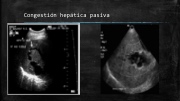

Congestión hepática pasiva